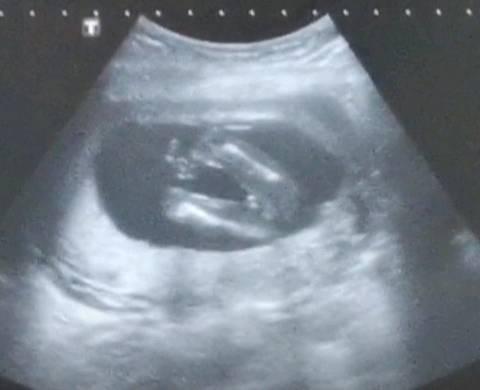

12周男孩女孩分化图,彩超三个月男胎儿图片

12周的nt 看着像男孩还是女孩

12周3天拍的b超,医生说看不清男孩女孩,好像是个女孩.

16周b超图看男孩女孩

12周做nt心率180是不是有点快,宝妈们能看出男孩女孩吗?

b超看男孩女孩图12周

12周胎儿图片真实图片

12周b超单子上看男女